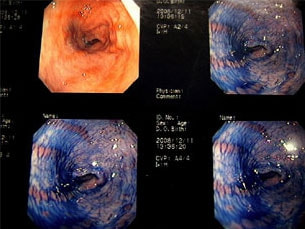

内視鏡下写真

内視鏡検査所見:胃内に竹串の先端部分が残っていたため、異物鉗子にて摘出しました。胃内は、全体的に炎症を伴い、出血している部位も確認されました。摘出後は、胃粘膜保護薬・プロトンプインヒビター(胃薬)の内服2剤ならびに食事療法により経過は良好です。